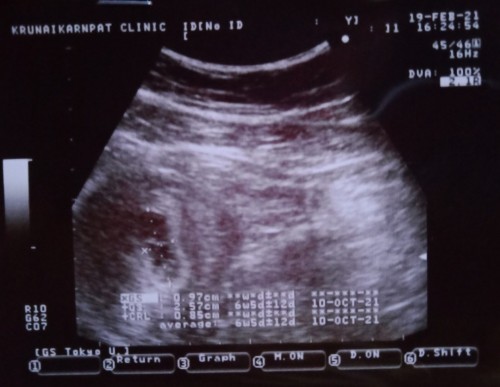

🥳เห็นน้องแล้วค่ะ ตอน9w1d แต่ก่อนหน้านั้นไปซาวตอน 4wเห็นแต่ถุง 5wก้ยังเห็นแต่ถุง 6wก้ยังเห็นแต่ถุง เริ่มเครียดค่ะ กลัวท้องลม แต่หมอก็นัดอีกทีตอน9w วันนี้เห็นแล้วค่ะ ดีใจมากๆๆ อยากจะเป็นกำลังใจให้แม่ๆที่ยังไม่เห็นนะคะ อย่าเครียดไปค่ะ เดี๋ยวก็ได้เจอตัวเล็กนะคะ 😘